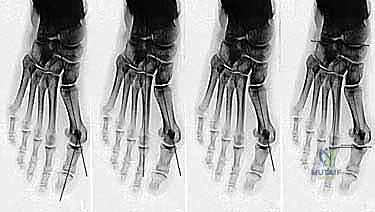

- التصوير بالأشعة السينية الدقيقة (Weight-Bearing X-Rays): وهي خطوة حاسمة. يجب أن تؤخذ الأشعة والمريض واقف (يحمل وزنه على قدمه) لإظهار الحجم الحقيقي للتشوه.

- القياسات الهندسية لزوايا القدم: يقوم الدكتور هطيف بقياس زوايا محددة لتحديد نوع الجراحة، أهمها:

- HVA (Hallux Valgus Angle): زاوية انحراف الإبهام (الطبيعي أقل من 15 درجة).

- IMA (Intermetatarsal Angle): الزاوية بين العظمة المشطية الأولى والثانية (الطبيعي أقل من 9 درجات).

- DMAA (Distal Metatarsal Articular Angle): زاوية سطح المفصل، وهي الزاوية الأهم التي تحدد الحاجة لتقنية "ش